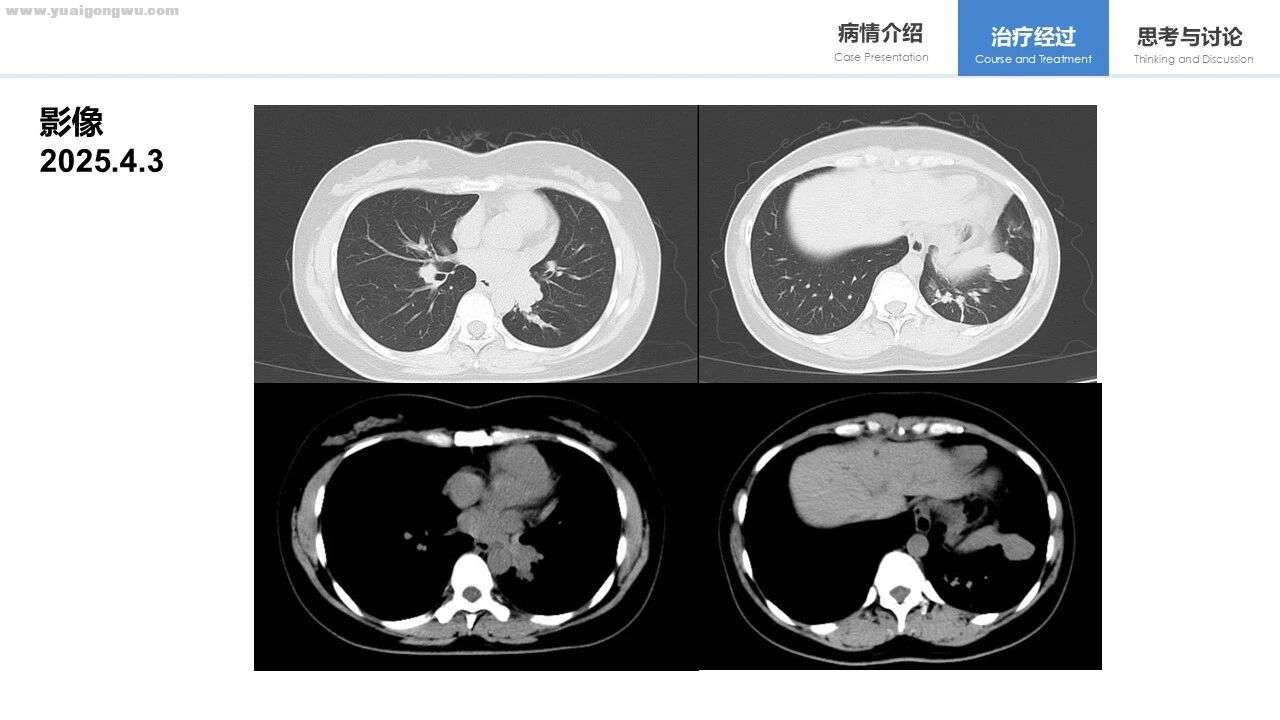

术后出现复发,双肺多发结节、胸膜结节及右侧肾上腺占位均呈高代谢,提示病变进展。治疗后,2025年4月与1月的影像对比显示,右上肺部分层面有好转,但左上肺个别病变看似增大(可能因体位或层面不一致所致,具体以报告为准),总体呈稳定状态。

王群慧教授 由于影像截图来自云胶片,有时定位可能不够精准,但依据现有报告,肺部整体变化处于稳定状态。6月与7月的腹部影像报告显示,病灶最长径无变化,仅短径存在变化。该患者接受了新辅助治疗及手术,术前根据PET-CT所示的高代谢淋巴结位置判断,分期接近Ⅲb期。对于此类患者,通常会如何处理?其纵隔内右上气管旁的淋巴结位置,大致接近2R及4R区。